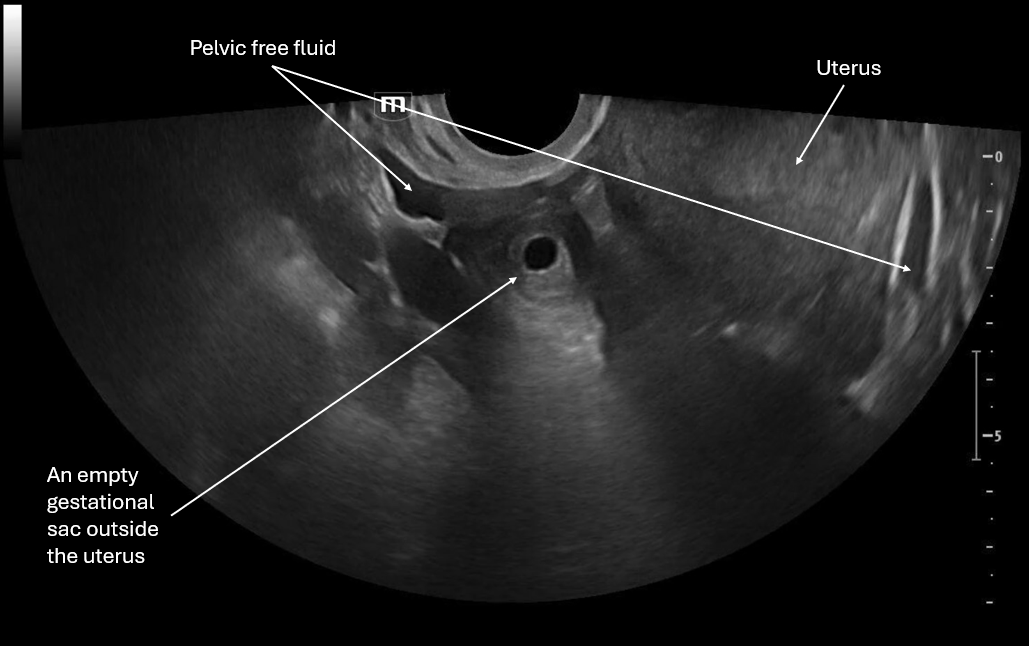

This image is a transverse view of the uterus where the probe marker is towards the patient's right. There is the fundus of the uterus in the middle of the screen and on the patient's right there is what appears to be an empty gestational sac and again we see pelvic free fluid.

This image focuses on what appears to be an empty gestational sac outside the uterus and we again see pelvic free fluid.